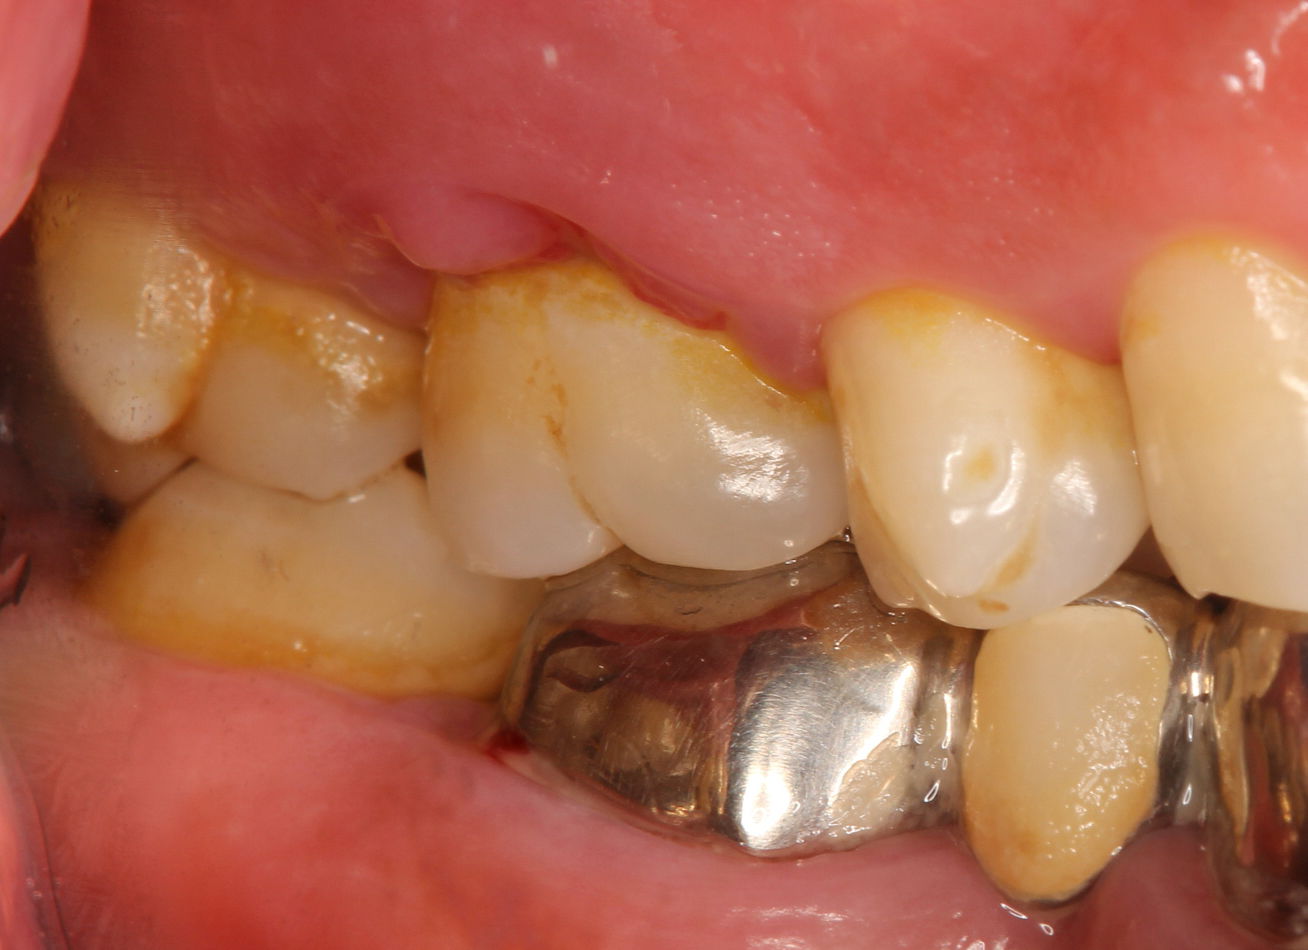

写真は初診時のものですが、口腔内全体が重度歯周病であり、上顎の第一大臼歯(⇓)周囲の歯肉の炎症も非常に強く認められます。

歯周基本治療を行い、歯肉の炎症も大分改善はしましたが、根分岐部がからんでおり、歯周ポケットは深い部位で8mmを示しました。